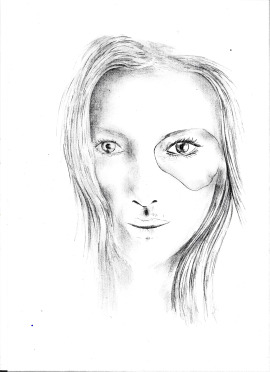

EPITHESE FACIALE COMPLEXE

Une épithèse faciale complexe est une prothèse sur mesure utilisée pour restaurer l'apparence d'un visage partiellement ou complètement détruit à la suite de traumatismes, de malformations congénitales, ou après une chirurgie pour traiter des cancers. Contrairement aux épithèses plus simples (comme les épithèses auriculaires ou nasales), une épithèse faciale complexe peut inclure plusieurs éléments du visage, comme le nez, les joues, les lèvres, les yeux ou même le menton, afin de recréer une apparence naturelle du visage.